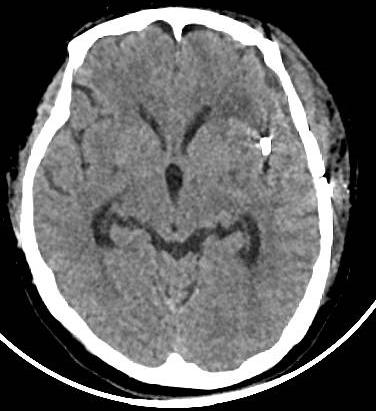

入院后完善术前相关检验检查,排除手机禁忌症后,急诊行翼点入路颅内动脉瘤夹闭术